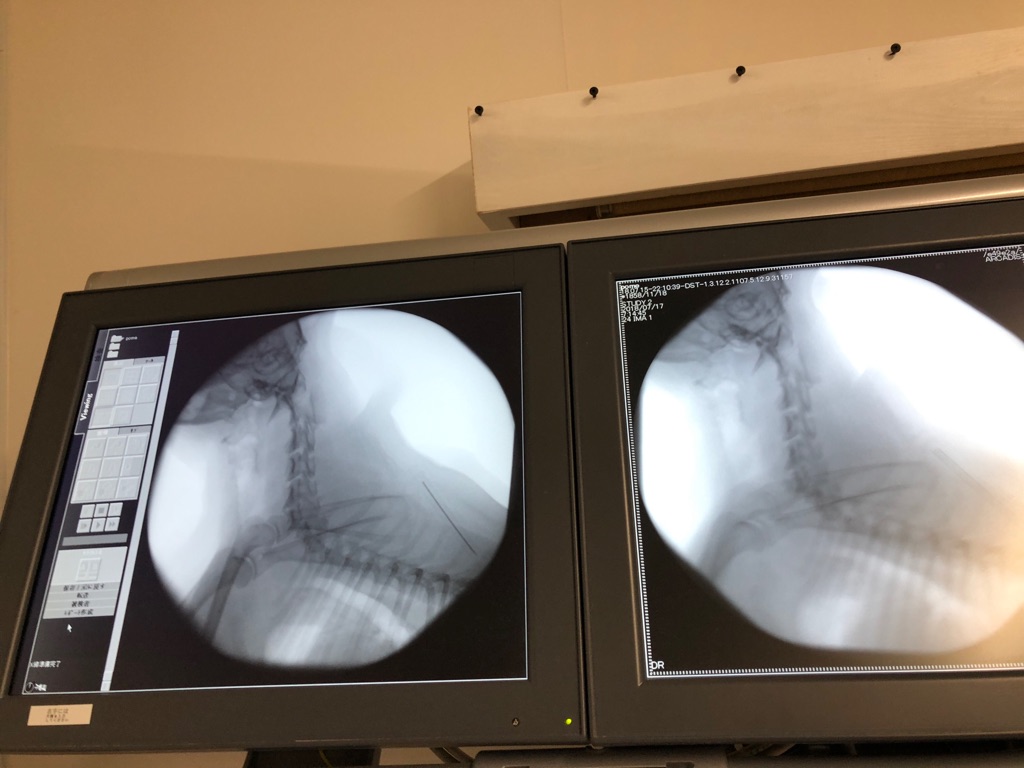

このポメ君は 先日のレスキューで来た子です、

呼吸が ゼイゼイ ヒューヒュー言って苦しそうでした、昨夜 ゴールデンを八匹降ろしていたら

先生が来てくださって 診察をして下さったのです。

結果は 気管虚脱で した、苦しそうだからなるべく早くに手術をしましょうと、、、

急遽今日の夜 都合をつけて手術に来てくださる事になりました。